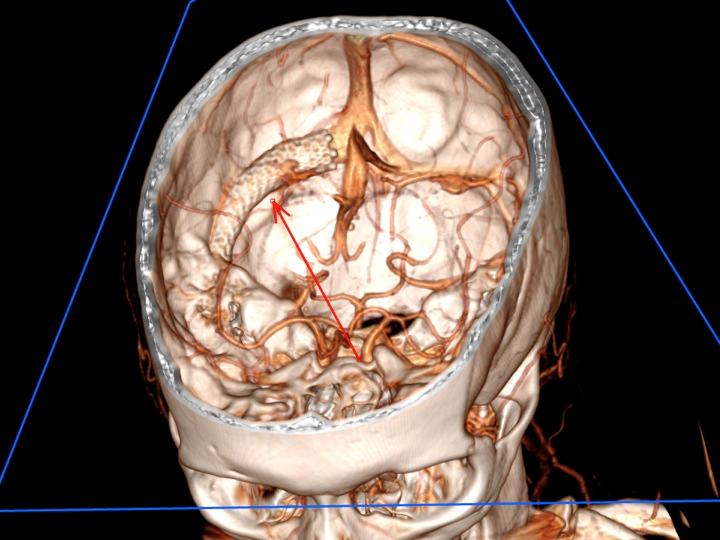

A 3D reconstruction showing the placement of an intracranial venous stent